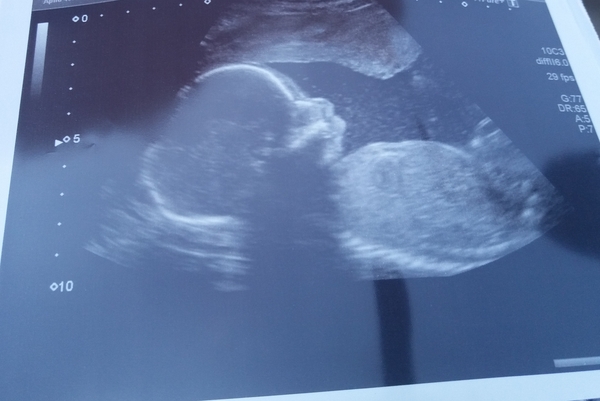

Omg omg omg. Scan was all fine, I'm also having a boy! Dh and I cried, it was so embarrassing but we were so relieved that Bean is well and thriving!

Eek I forgot the picture of the little dude.

@Athers666 sorry I posted that just now after writing it this morning and then I saw your scan pic! Gorgeous! Did you know you were having a boy already!! Sorry lost track from the old thread! His profile is so cute. And he looks so chilled!!!

@Athers666 total baby brain today.. just read your previous statement! So massive congrats for boy!!! Looks like December is full of them!!! 💙😍

Lovely to see your scans @Athers666 and @cakelaur congrats on your boys.